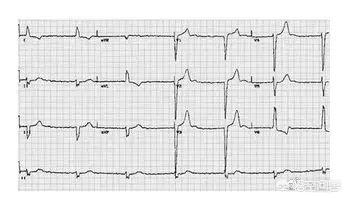

心电图是实践技能考试的必考内容,心电图虽然复杂,但是实践技能考试大纲所要求考查的心电图的难度不是很大,特意给大家整理了心电图的速记口诀,希望对大家复习有所帮助!

1、正常心电图:不用说了,它有可能是把那几个波和导联都斩一段下来,每一个波给你3个周期,分成几行给你看,要注意。(P,QRS,T波;PR,QT间期)

2、左心室肥大:只要看V5大于5格,是上下纵的5格(即V5导联QRS波>0.25mV)

3、右心室肥大:只要看V1大于2,格,是上下纵的2格(即V1导联QRS波中R/S>1,也就是R波>S波的幅度)

4、心房颤动:所有的P——P,Q——Q,R——R,S——S,T——T都没规律,也就是P波的位置上乱七八糟的。可发展为心室颤动。(即P波的位置被大小不一的小f波取代,而QRS波正常)

5、心室颤动:所有的P——P,Q——Q,R——R,S——S,T——T都没规律,正常QRS波消失,只剩下大小不一的小波。

9、典型心肌缺血:V4,V5,V6的ST段下移

10、急性心肌梗死:Q波增宽+ST段弓背向上抬高,注意:前壁看V1,V2,V3,V4,V5,V6;下壁看Ⅱ,Ⅲ,aVF